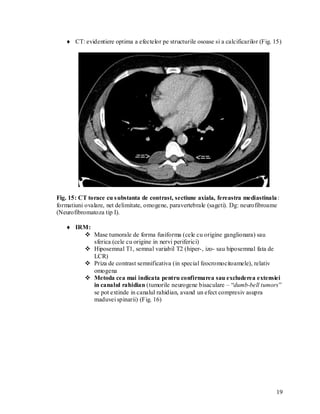

 CT: evidentiere optima a efectelor pe structurile osoase si a calcificarilor (Fig. 15)

Fig. 15: CT torace cu s ubstanta de contrast, sectiune axiala, fereastra mediastinala :

formatiuni ovalare, net delimitate, omogene, paravertebrale (sageti). Dg: neurofibroame

(Neurofibromatoza tip I).

 IRM:

 Mase tumorale de forma fusiforma (cele cu origine ganglionara) sau

sferica (cele cu origine in nervi periferici)

 Hiposemnal T1, semnal variabil T2 (hiper-, izo- sau hiposemnal fata de

LCR)

 Priza de contrast semnificativa (in special feocromocitoamele), relativ

omogena

 Metoda cea mai indicata pentru confirmarea sau excluderea extensiei

in canalul rahidian (tumorile neurogene bisaculare – “dumb-bell tumors”

se pot extinde in canalul rahidian, avand un efect compresiv asupra

maduvei spinarii) (Fig. 16)